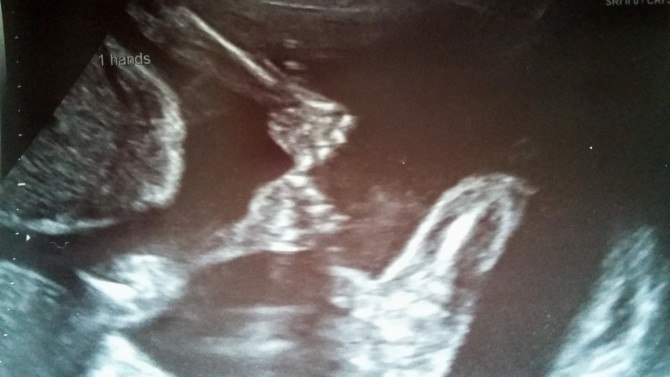

bayi kembar pegangan tangan di dalam rahim

rowan dan Blake di dalam rahim tampak berpegangan tangan. sumber: metro.co.uk

Hayley dibuat takjub karena setiap kali melakukan scan, ia melihat kedua bayinya sedang berpegangan tangan. Bayi kembar Hayley dilahirkan prematur secara caesar pada 25 Agustus 2016.